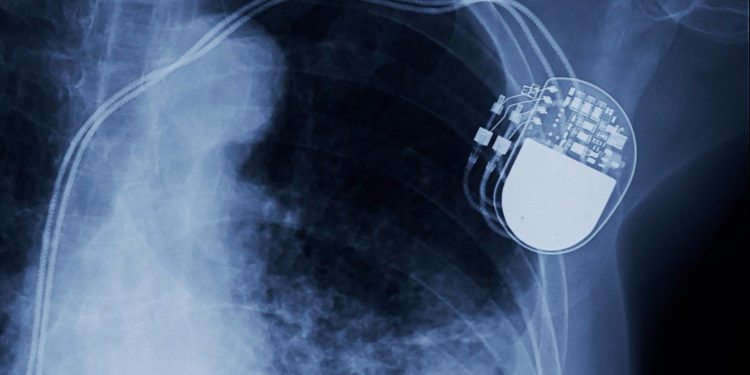

Управление по контролю за продуктами и лекарствами США (US Food and Drug Administration) объявило о отзыве нескольких моделей кардиостимуляторов, произведенных компанией Abbott, поскольку эти устройства оказались уязвимыми для хакеров, пишет сайт Motherboard.

Баг в программном обеспечении кардиостимулятора позволяет хакерам с небольшого расстояния получить контроль над устройством и замедлять или ускорять биение сердца человека, что может привести к смерти больных.

Под ударом оказалось почти 465 тысяч пациентов, которых в настоящее время вызвали для перепрошивки программного обеспечения кардиостимуляторов.